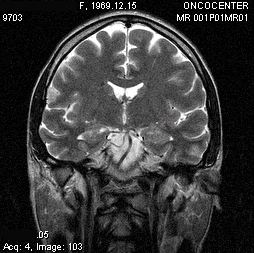

Всем пациентам в процессе курса и после брахитерапии проводили МРТ контроль в ранние сроки. Уже на 10-15 сутки после курса терапии наблюдали изменения МРТ структуры и размеров опухоли. При этом перифокальный отёк был выражен минимально ввиду особенности метода и точного подведения дозы. В дальнейшем КТ или МРТ контроль проводили через 1, 3, 6, 12 месяцев.

Описываем клинический случай стереотаксической брахитерапии, выполненной в Уральском межтерриториальном нейрохирургическом центре (ГБУЗ СО Свердловский областной онкологический диспансер), пациентке К. 31 год с глиальной опухолью диэнцефальной области (дна III желудочка). Данные МРТ головного мозга представлены на слайдах.

7. МРТ контроль спустя 4 месяца после брахитерапии. Отмечается положительная динамика в виде регресса опухоли.